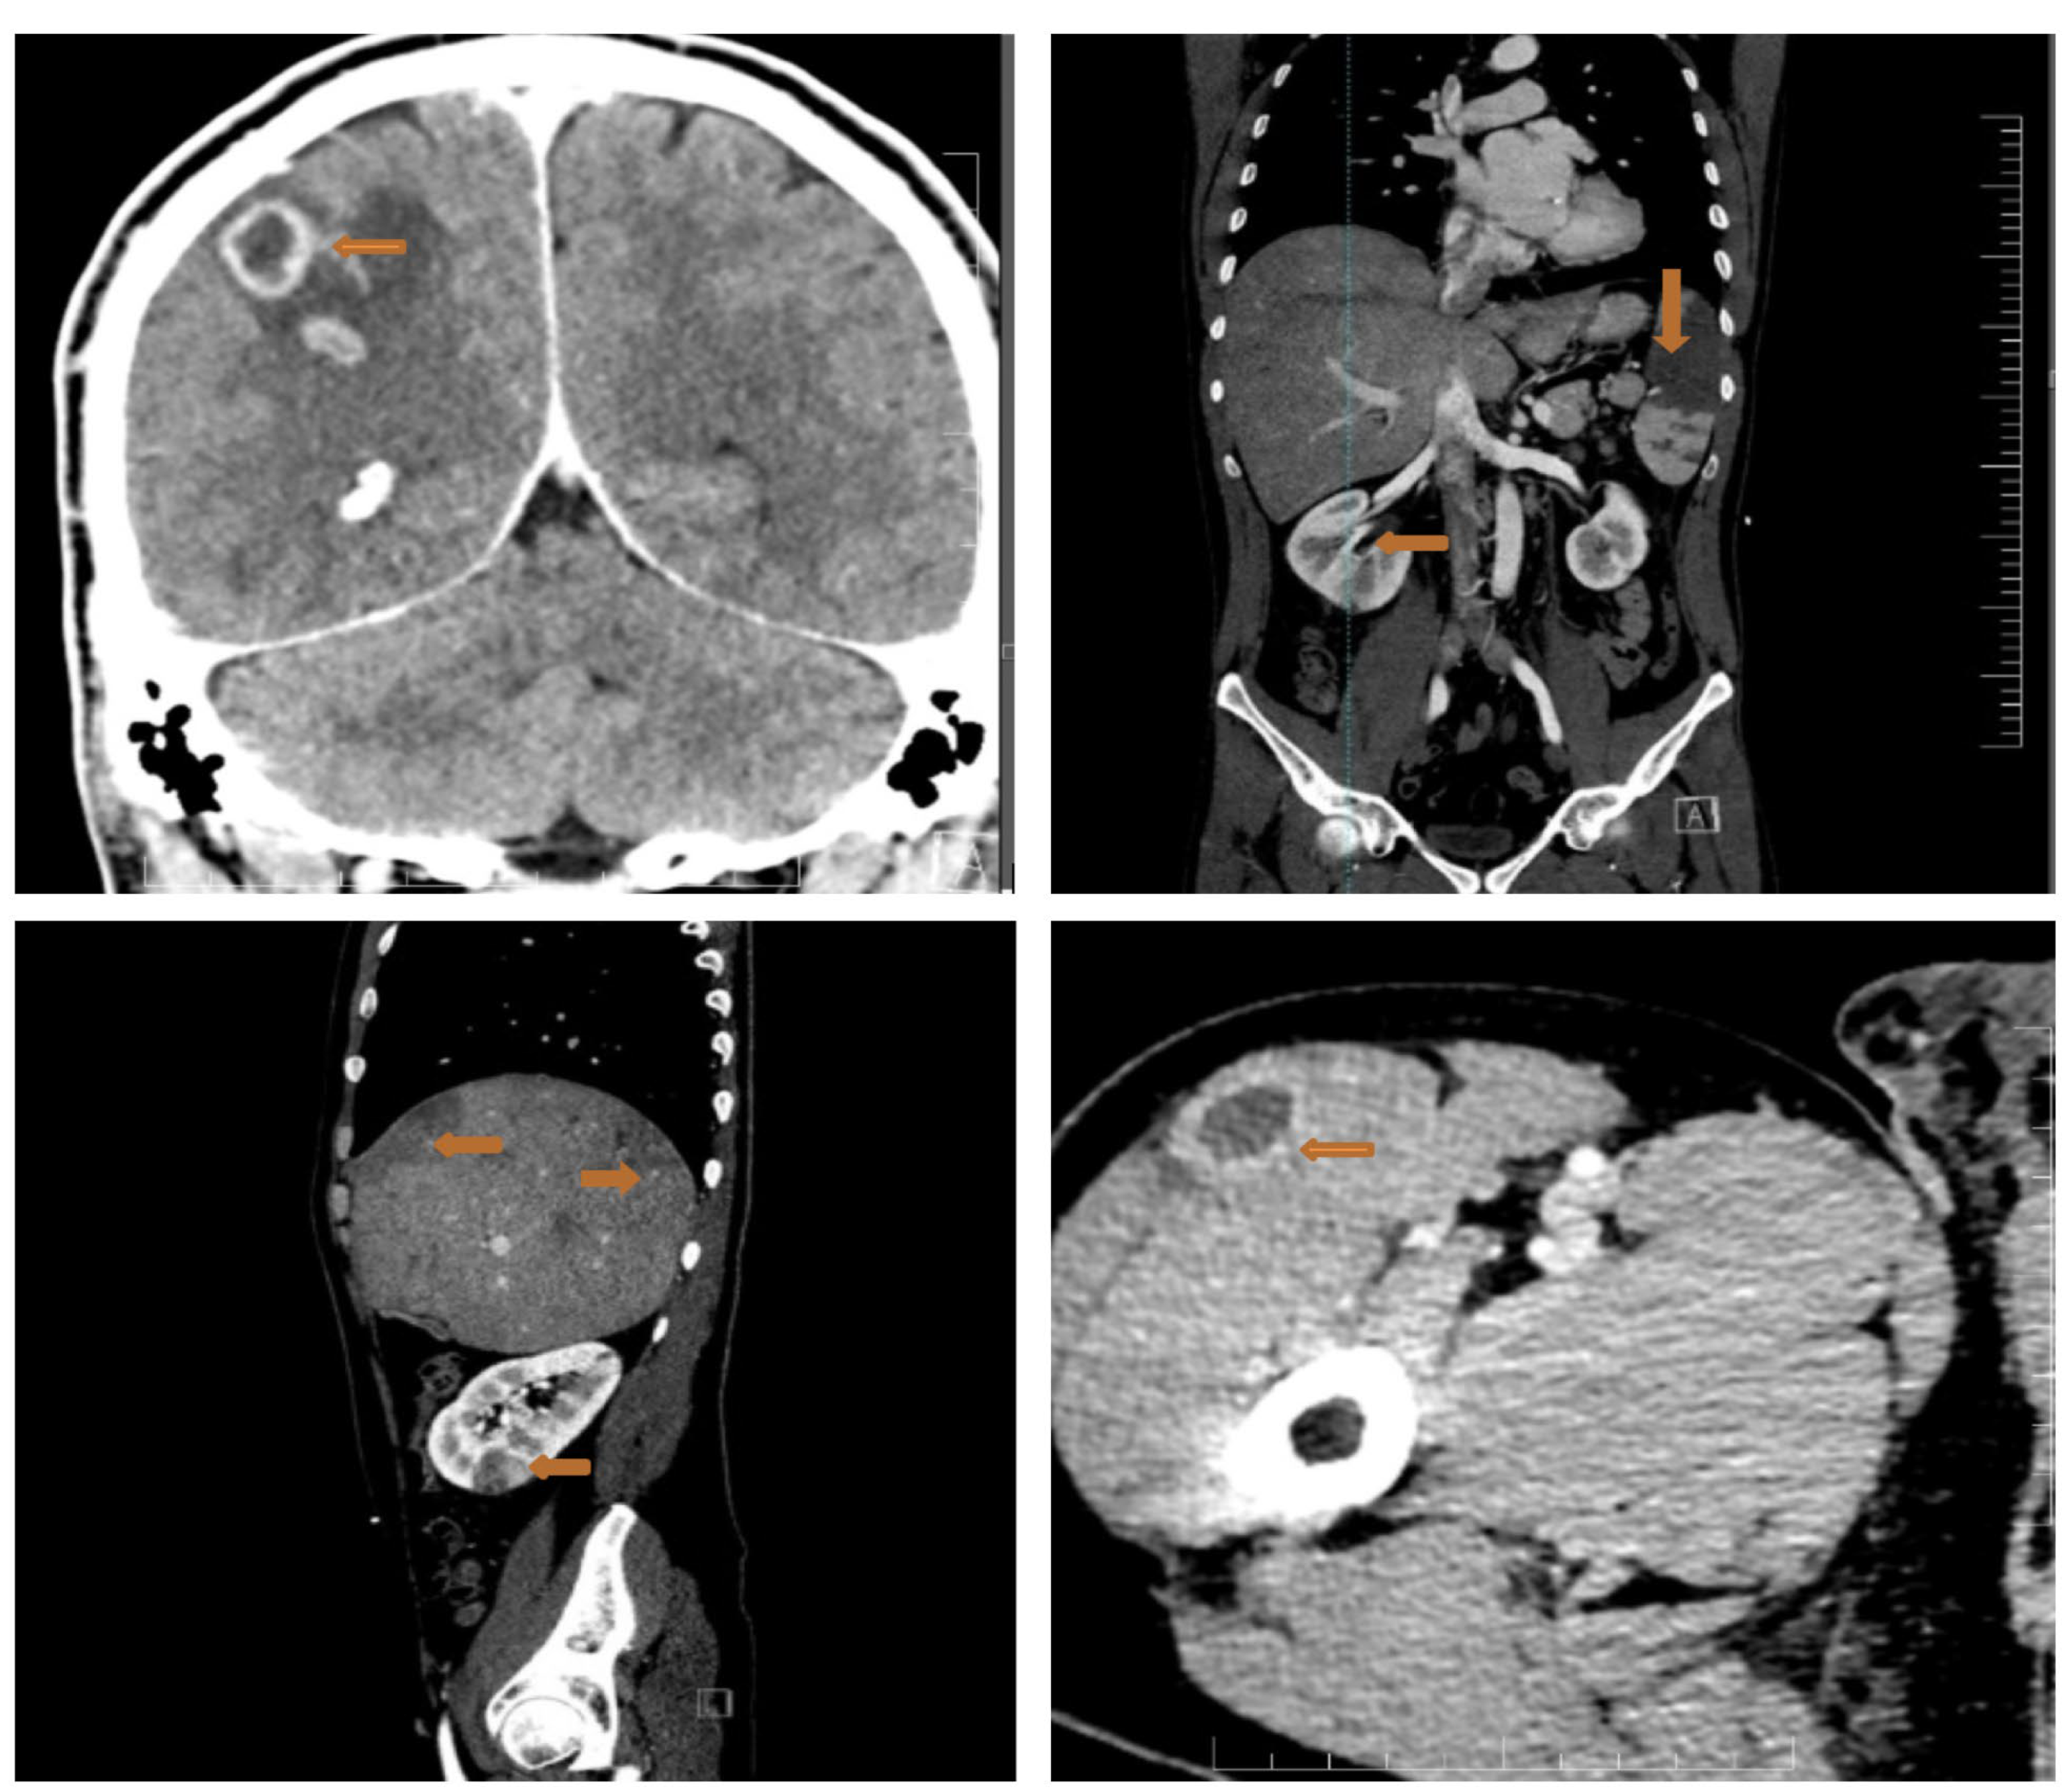

2. Case Report